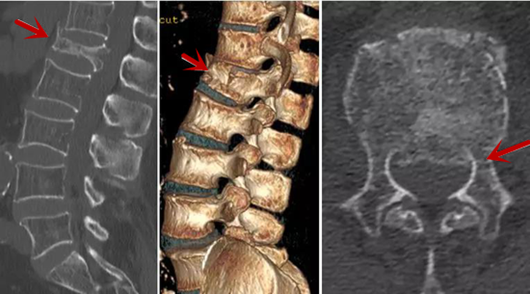

利器二:CT

CT利用X射線對人體檢查部位通過電腦切成若干層掃描,然后把每層的圖像都能顯示出來。CT相對于X光片具有更高的密度分辨力,可直接顯示X線片無法顯示的病變,觀察腰椎有無微小的骨折、骨質(zhì)有無破壞等骨質(zhì)情況、以及腰椎間盤突出、腰椎神經(jīng)根、椎管、椎間小關(guān)節(jié)的情況等。同時還可以通過后處理,重建腰椎矢狀位或冠狀位圖像,形成腰椎的3D圖像,更直觀地觀察病變部位,對腰椎手術(shù)風(fēng)險具有提示作用,對手術(shù)方式的選擇具有指導(dǎo)意義,但是對神經(jīng)、脊髓損傷程度的顯示不如MRI,軟組織的分辨率仍有一定限制,對椎管內(nèi)病變顯示欠佳,且有一定的輻射。

箭頭提示椎間盤突出

從左向右依次為CT矢狀位重建圖像、三維重建圖像、軸位掃描圖像,箭頭提示腰1椎體爆裂性骨折